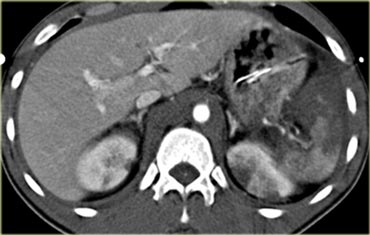

Trước tiên hãy quan sát các hình ảnh bên trái của bệnh nhân bị chấn thương gan.

Các dấu hiệu CT trong trường hợp này là gì?

Các dấu hiệu bao gồm:

- Tụ máu dưới bao gan lớn hơn 10 cm (tức là tổn thương độ 4)

- Vùng ngấm thuốc cản quang (contrast blush) (mũi tên)

- Không có tràn máu ổ bụng kèm theo

Vì vậy, mặc dù có thoát thuốc cản quang, bệnh nhân này sẽ được điều trị bảo tồn (không phẫu thuật) và có thể có tiên lượng tốt, do không có chảy máu vào khoang phúc mạc.

Thoát thuốc cản quang có ý nghĩa đặc biệt quan trọng, nhất là khi kết hợp với tràn máu ổ bụng.